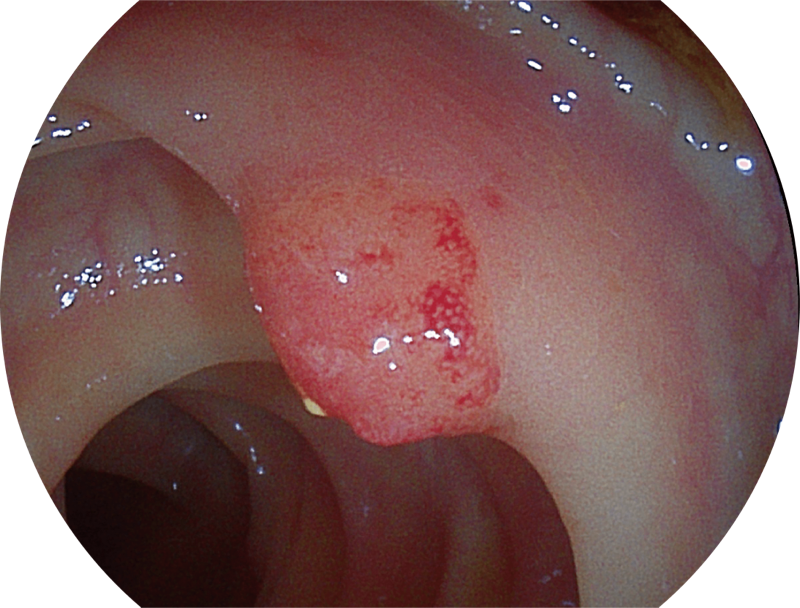

百万级像素高清传感器,1080P全高清视频信号输出,图像清晰。

能够凸显黏膜浅层血管轮廓和黏膜表面微结构,适用于中、近景观察下的早癌精确诊断。